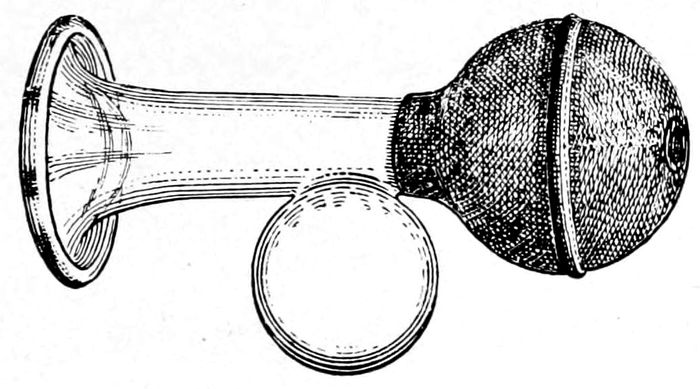

| 110. |

A standard breast pump |

251 |